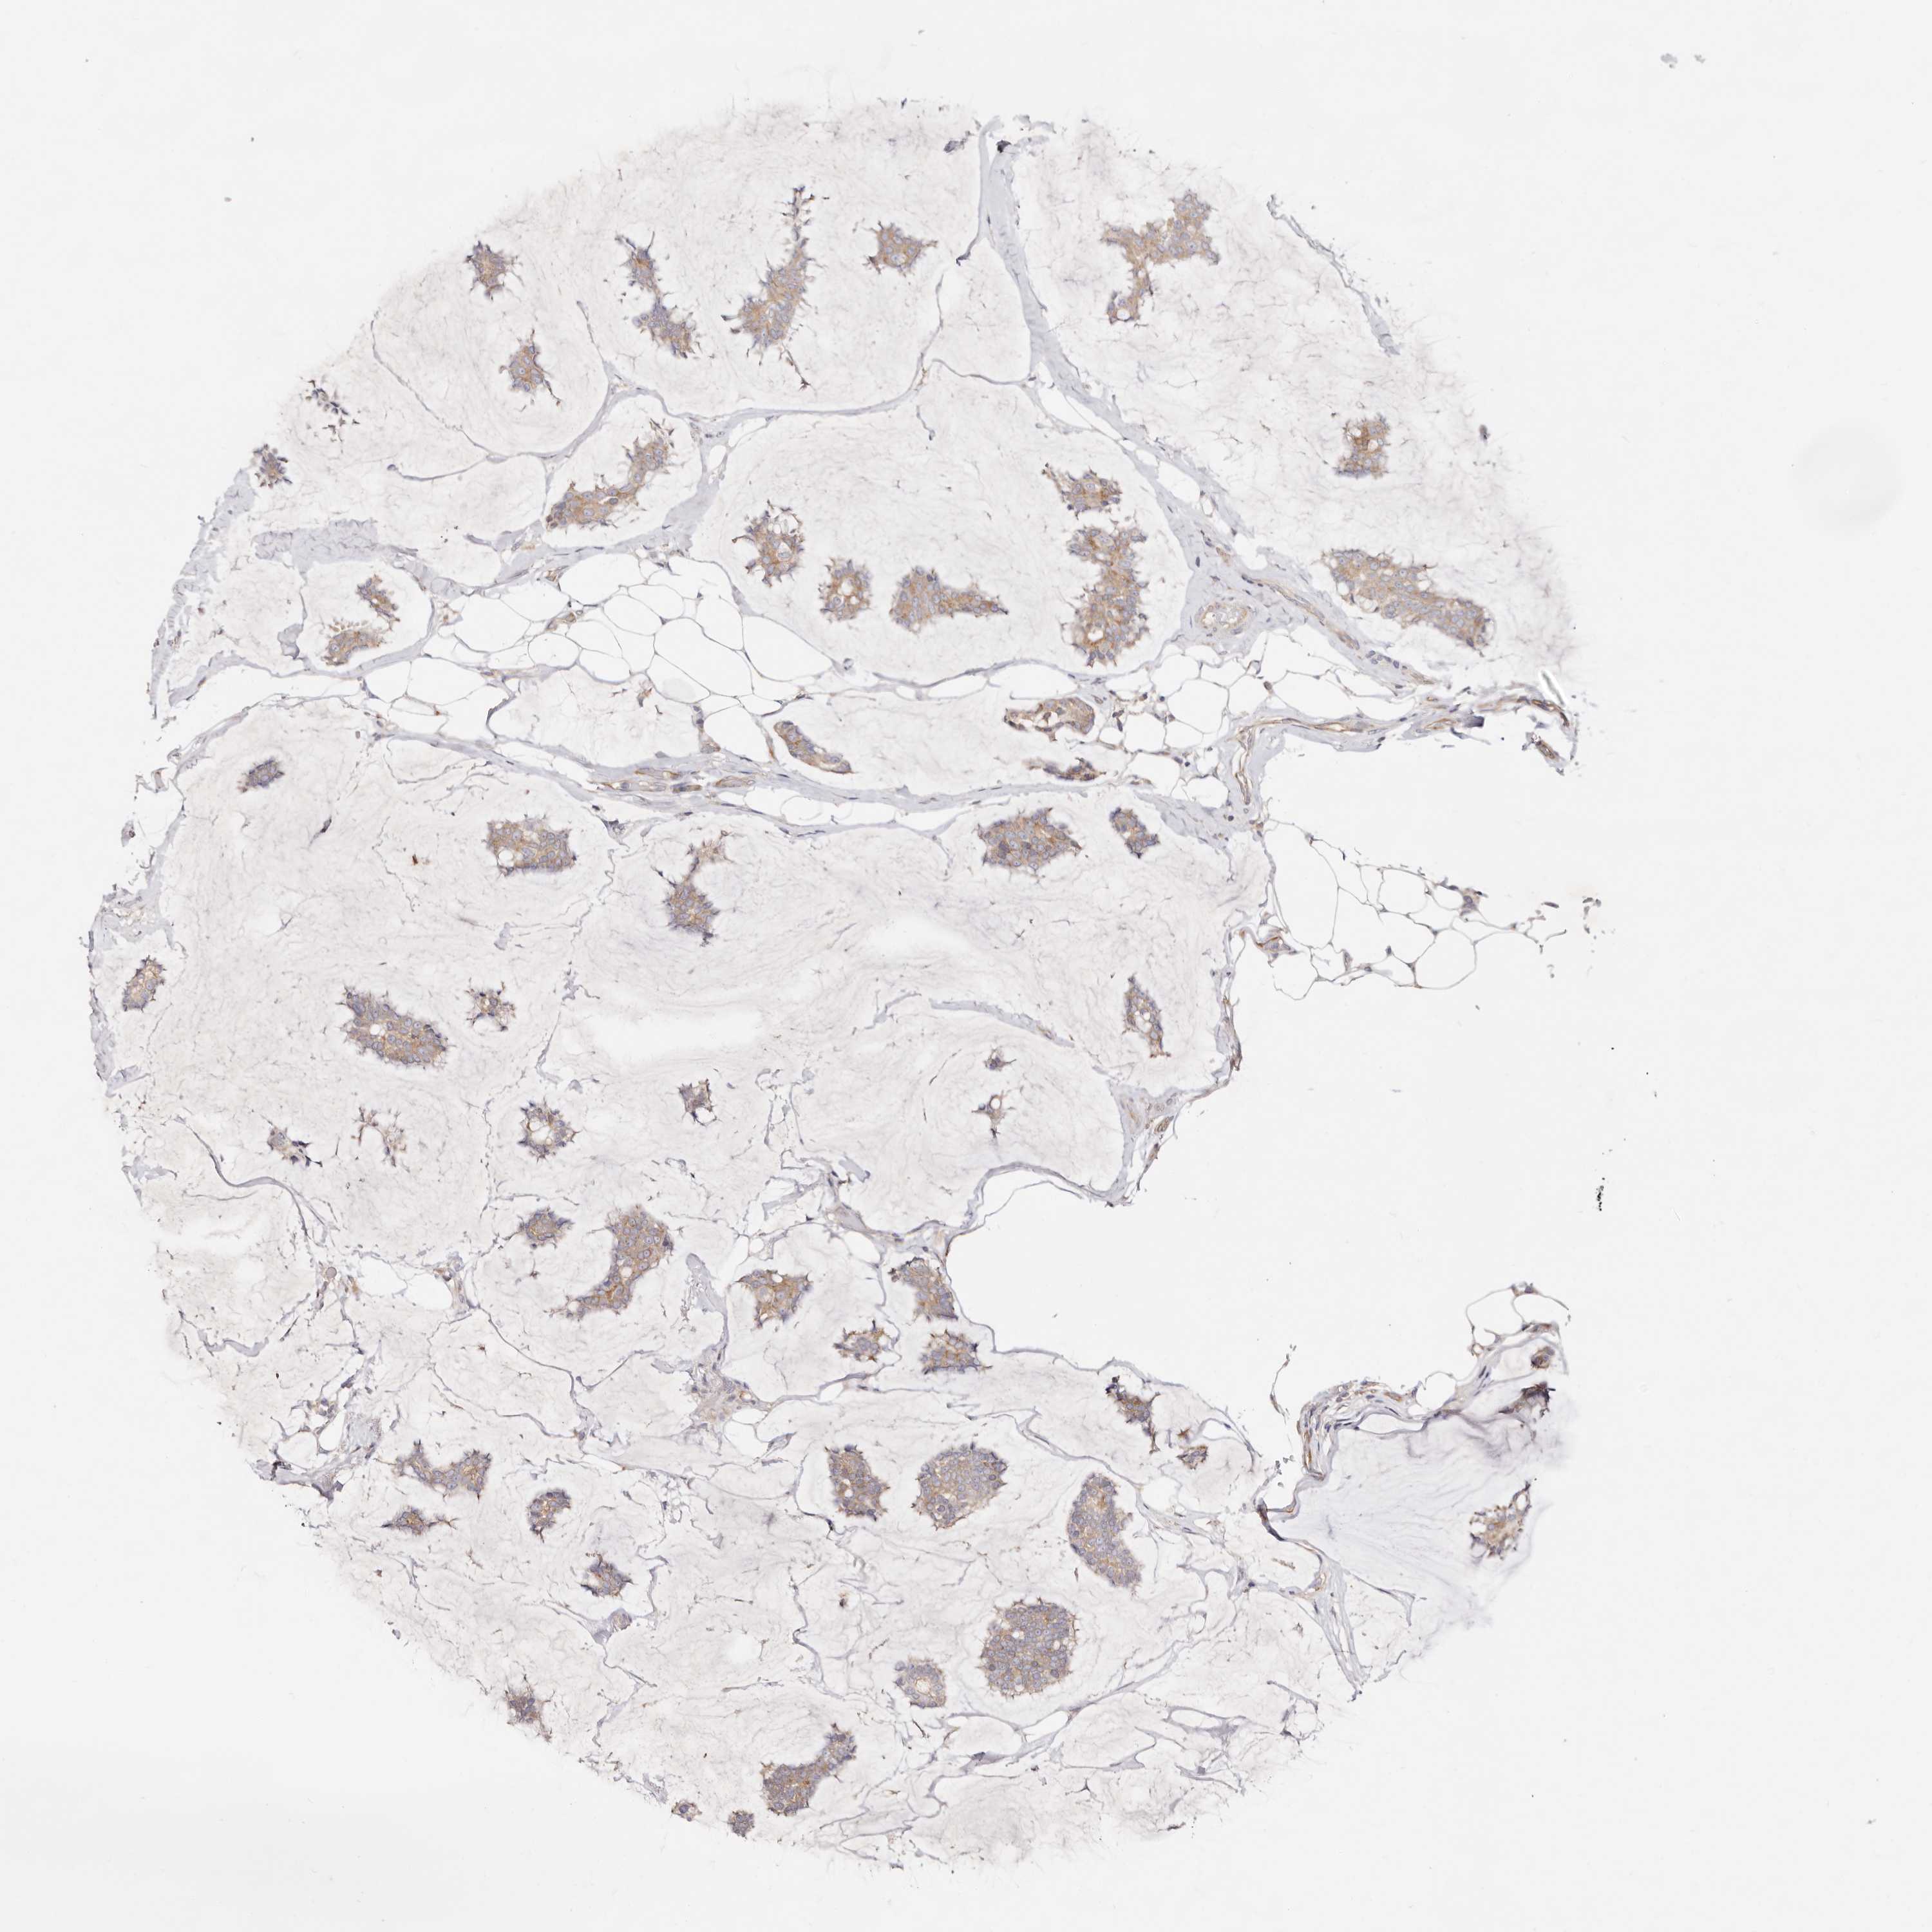

Breast cancer

Human cancer